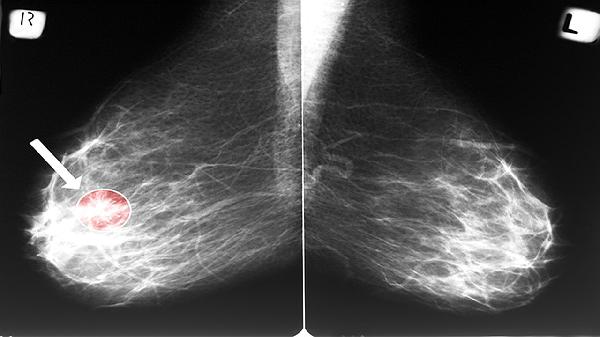

肾上腺CT扫描是诊断肾上腺肿瘤的首选方法,能清晰显示肿瘤的大小、位置、密度以及与周围组织的关系。增强CT可进一步评估肿瘤血供情况,有助于鉴别良恶性。肾上腺MRI检查对软组织分辨率更高,适用于评估肿瘤与血管的毗邻关系,尤其对肾上腺嗜铬细胞瘤的诊断有重要价值。